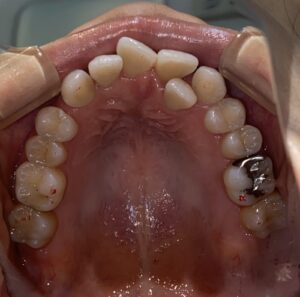

IMG_2972

2024年4月9日

MT初診時上顎8番抜歯後